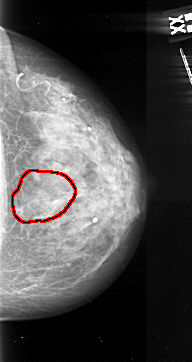

A_1058_1.RIGHT_MLO

RIGHT_MLO LINES 5491 PIXELS_PER_LINE 2761 BITS_PER_PIXEL 16 RESOLUTION 42 OVERLAY

FILE: A_1058_1.RIGHT_MLO.OVERLAY

TOTAL_ABNORMALITIES 1

ABNORMALITY 1

LESION_TYPE MASS SHAPE ARCHITECTURAL_DISTORTION MARGINS SPICULATED

ASSESSMENT 5

SUBTLETY 5

PATHOLOGY MALIGNANT

TOTAL_OUTLINES 1

BOUNDARY